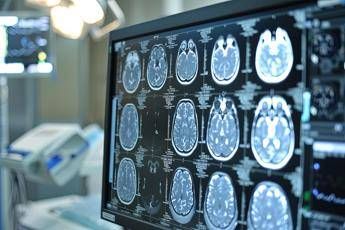

(Adnkronos) – A pochi giorni dalla diffusione dei risultati preliminari globali dello studio di fase 3 Oceanic-Stroke, Bayer Italia sottolinea il contributo del nostro Paese a un trial che potrebbe aprire un nuovo capitolo nella prevenzione secondaria dell'ictus ischemico non cardioembolico. Lo studio, che ha valutato l'inibitore del Fattore XIa asundexian in aggiunta alla terapia antiaggregante – informa una nota – ha mostrato una riduzione significativa del rischio di ictus ischemico rispetto al placebo, senza aumentare i sanguinamenti maggiori, raggiungendo così entrambi gli endpoint primari di efficacia e sicurezza. L'Italia ha dato un contributo importante alla ricerca con 22 centri clinici coinvolti in tutto il Paese. Grazie ai dati raccolti e alla gestione accurata del follow-up, i centri italiani hanno supportato lo studio in modo determinante, rafforzando la robustezza scientifica dei risultati globali. L'ictus rappresenta ancora una sfida di portata globale: ogni anno colpisce circa 12 milioni di persone e nel 20–30% dei casi si tratta di recidive. E' la seconda causa di morte nel mondo e le recidive spesso comportano esiti ancora più gravi rispetto al primo episodio. Nonostante le terapie oggi disponibili, il rischio di un nuovo evento rimane elevato: 1 sopravvissuto su 5 può andare incontro a un secondo ictus entro 5 anni. "Lo studio Oceanic-Stroke – afferma Andrea Zini, direttore della Neurologia e Rete Stroke dell'Irccs Istituto delle scienze neurologiche dell'ospedale Maggiore di Bologna – segna un cambiamento importante nella ricerca neurologica. Gli inibitori del Fattore XIa come asundexian rappresentano una nuova frontiera nella prevenzione dell'ictus, un passo significativo nella lotta contro le recidive, soprattutto per i pazienti con ictus ischemico non cardioembolico per i quali le opzioni terapeutiche non sono state sostanzialmente innovate negli ultimi anni. Asundexian, primo farmaco di questa classe a completare con successo uno studio di fase 3, potrebbe offrire una soluzione efficace per ridurre il rischio di ictus ricorrenti in questa popolazione. La terapia antiaggregante attualmente in uso non è sufficiente per prevenire completamente i secondi ictus, il che rende l'approvazione di nuovi trattamenti ancora più cruciale" Asundexian ha ottenuto la designazione fast track dalla Food and Drug Administration degli Stati Uniti come potenziale trattamento per la prevenzione dell'ictus nei pazienti con ictus ischemico non cardioembolico, ricorda la nota. Tuttavia – si legge – va sottolineato che asundexian è ancora un farmaco sperimentale e non è stato ancora approvato da alcuna autorità sanitaria. Lo studio Oceanic-Stroke ha analizzato efficacia e sicurezza di asundexian, inibitore orale del Fattore XIa, somministrato alla dose di 50 mg una volta al giorno, per la prevenzione dell'ictus ischemico in pazienti che avevano recentemente avuto un ictus ischemico non cardioembolico o un attacco ischemico transitorio (Tia) ad alto rischio. Il trattamento è stato valutato in combinazione con la terapia antipiastrinica standard. Si tratta di uno studio multicentrico e internazionale, randomizzato, controllato con placebo, in doppio cieco, a gruppi paralleli e guidato dal numero di eventi, che ha arruolato oltre 12.300 pazienti.